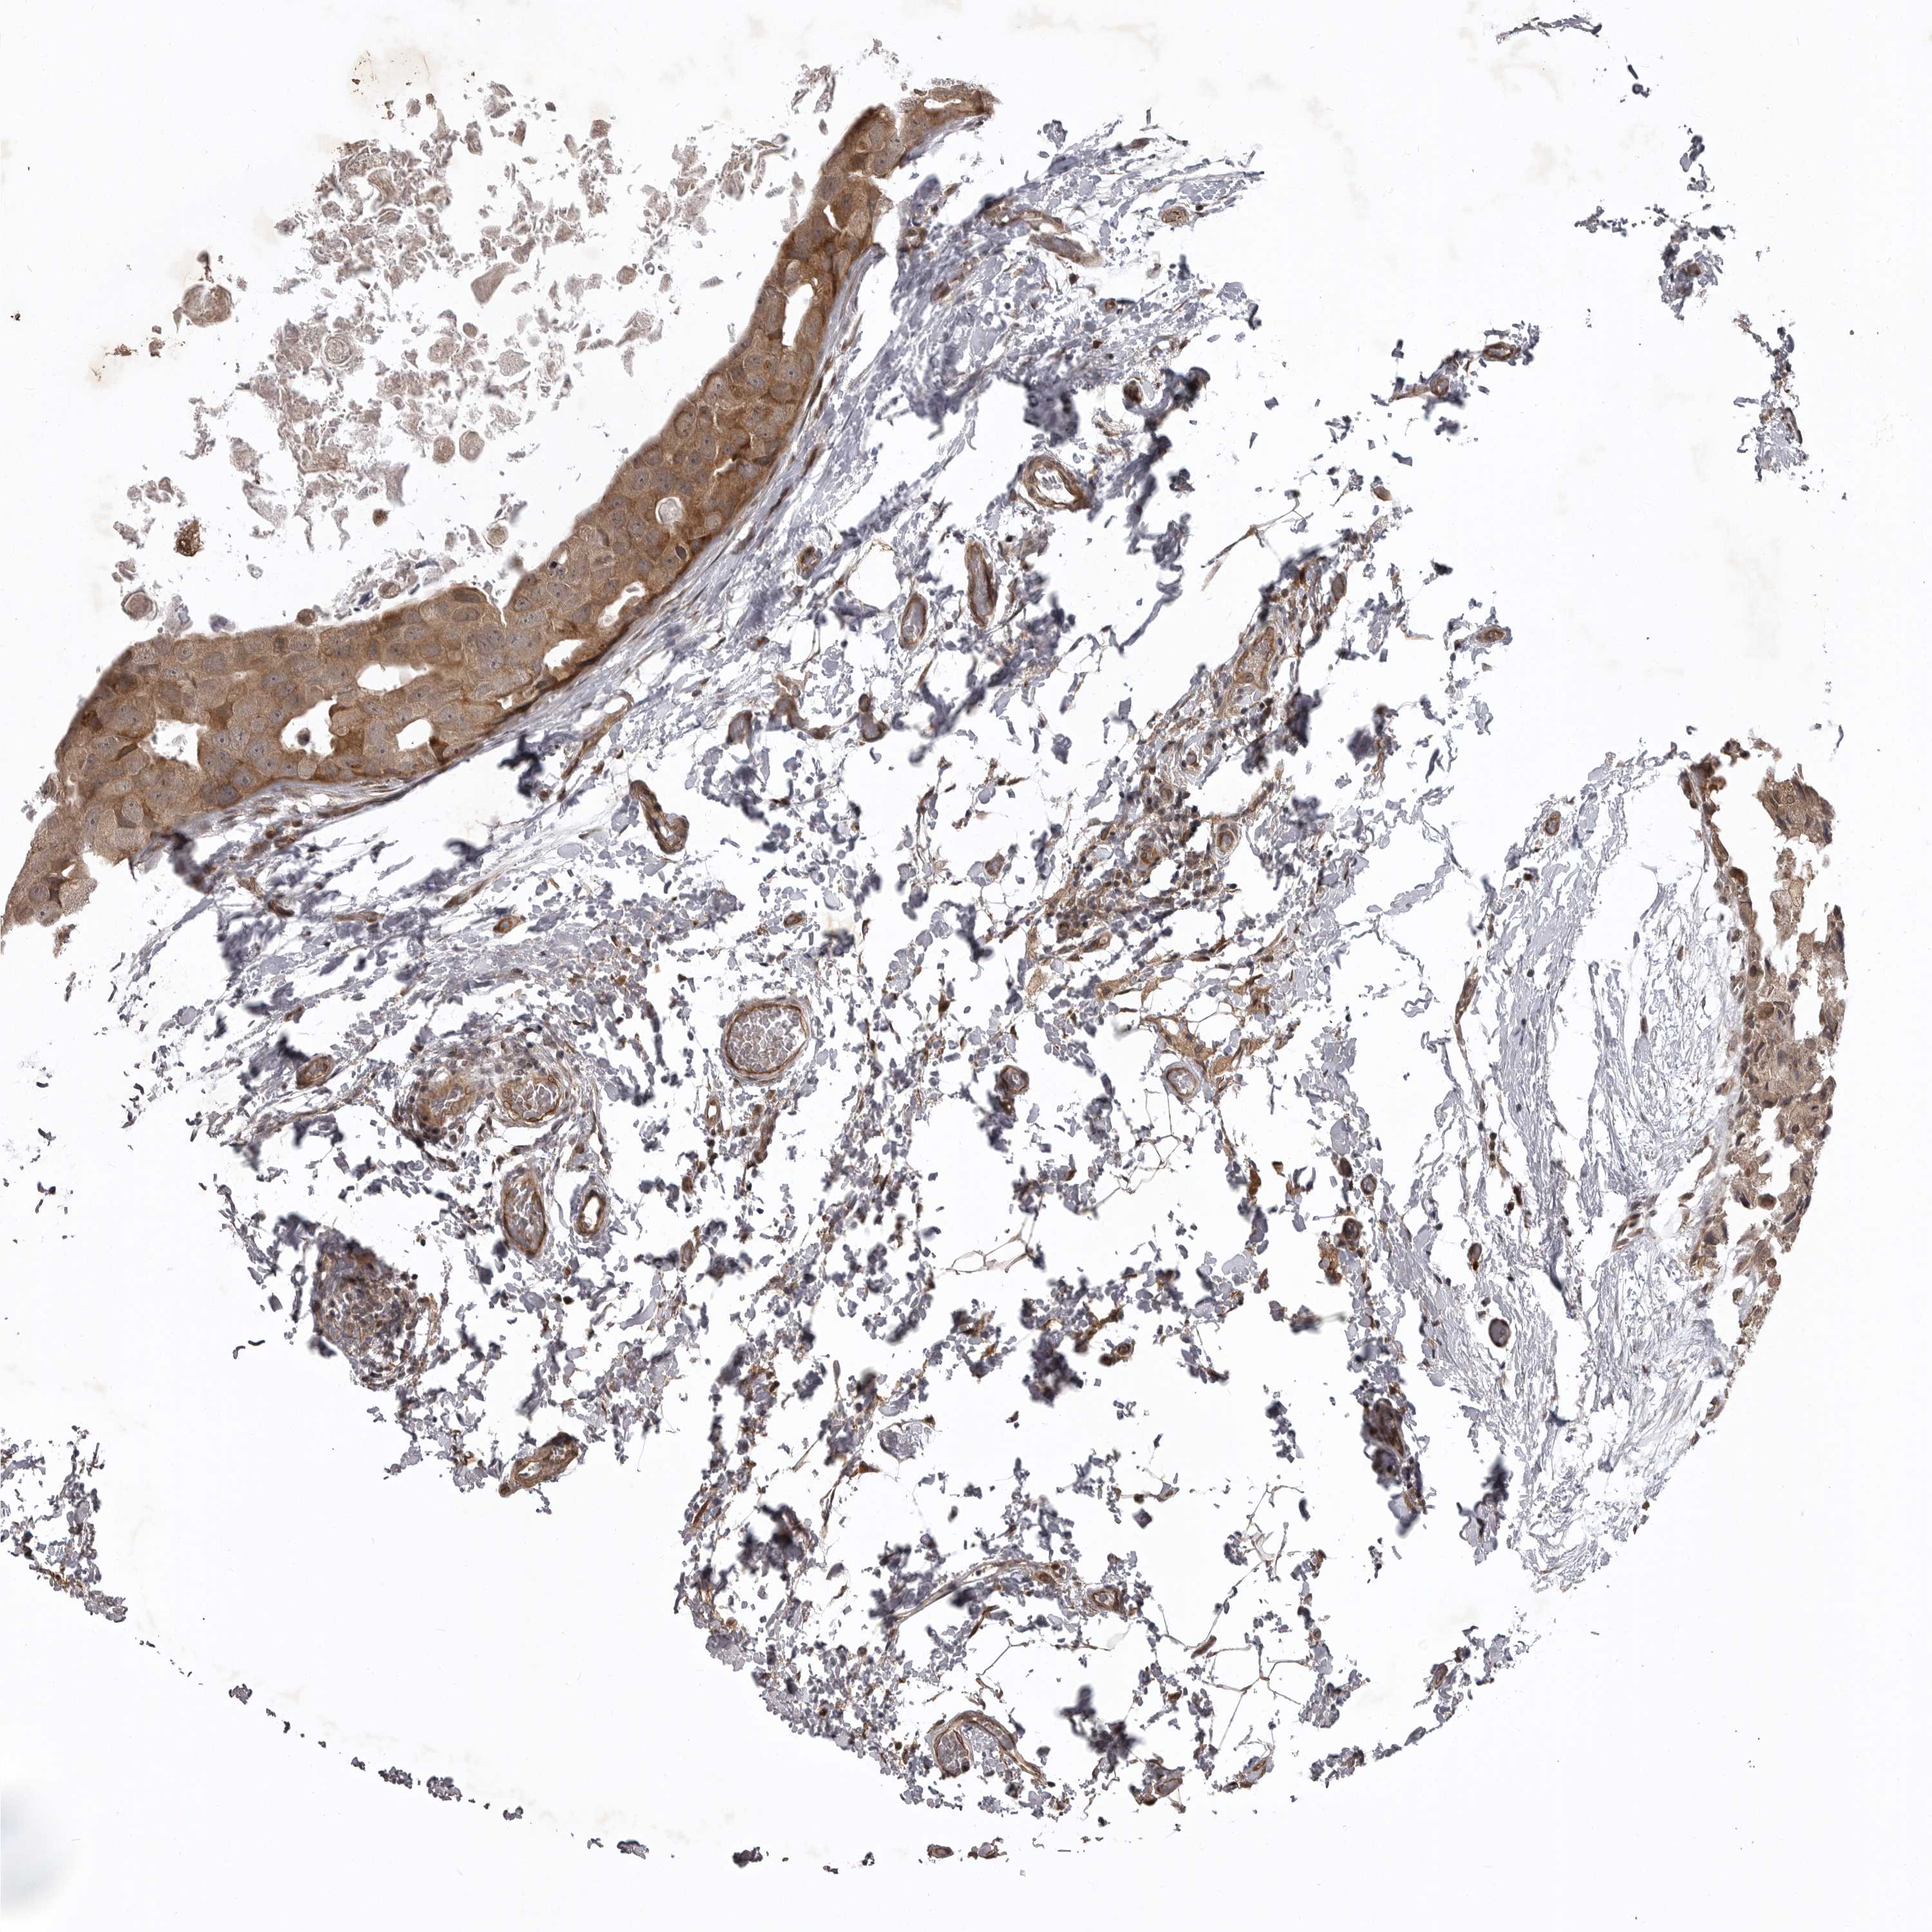

CANCER BREAST CANCER Show tissue menu

BRCA TCGA BRCA VALIDATION PROTEIN EXPRESSION